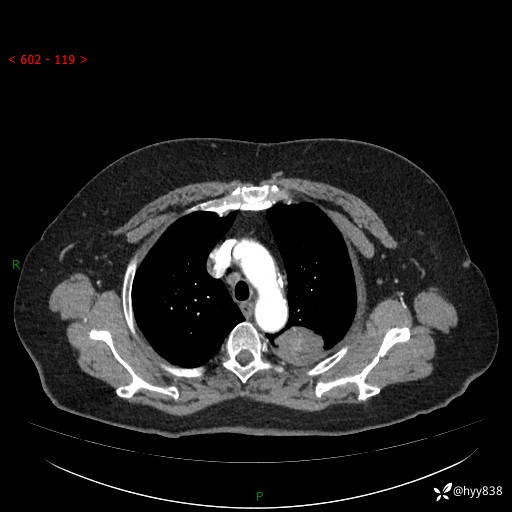

老年女性,左上肺结节8年。典型又不典型,看你如何解读---结果公布(值得分析)

主诉:检查发现左上肺结节8年,较前增大。

简要病史:患者于8年前体检行胸部CT检查发现左上肺结节(4mm),患者平素间断咳嗽咳痰,无心慌、胸闷、胸痛、呼吸困难、低热、盗汗,无头痛、头晕,无腹痛、腹胀等不适,未行特殊处理,定期复查。2023-09-21胸部CT示左上肺结节(2cm)较前增大,2024-02-01胸部CT示左上肺尖后段(39*32mm),左侧肺门及纵隔淋巴结增大,现患者欲求手术治疗,遂来我院就诊,以“左上肺结节”收入我科。 患者自起病以来,精神可,睡眠可,饮食可,大小便正常,体重无明显改变。

辅助检查:CT

胸部CT平扫

增强(动脉期+静脉期)